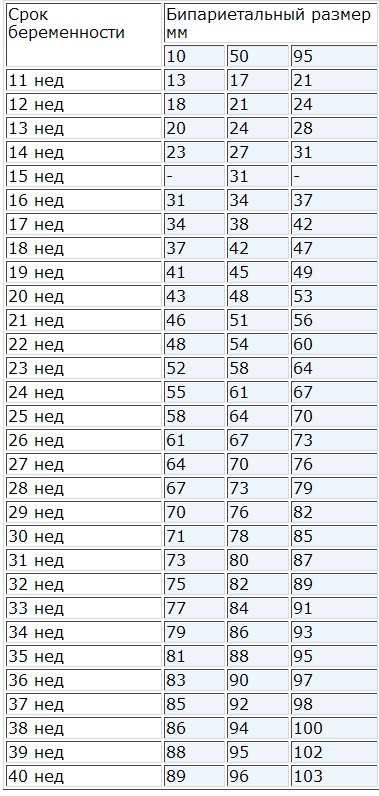

Има така наречените седмични стандарти на БДП, които са специално предназначени за всеки период от бременността, което значително улеснява диагнозата. Изследванията могат да се извършват върху най-важното, но най-точна информация за развитието на детето в съответствие с бременността са на втория или третия триместър на бременността.

За да разберете какво biparietal плода размер и дали е резултатите си с общо установените норми, е необходимо да се чете една маса, която представя данни за BDP всяка седмица. Тези таблици вече са включени в програмата на ултразвук апарат и той е на тази основа дава заключение. Операторът или на лекар независимо избран желания тип данни и е монтиран непосредствено пред собствено проучване. Не трябва незабавно да се паникьосвайте, ако окончателните резултати не са перфектни, винаги разрешени колебания в рамките на определени граници. Окончателната диагноза дали скоростта на BDP си бременността. Например, BDP 18 мм еквивалент присъщ както в 11-та и 12-та седмица на бременността.